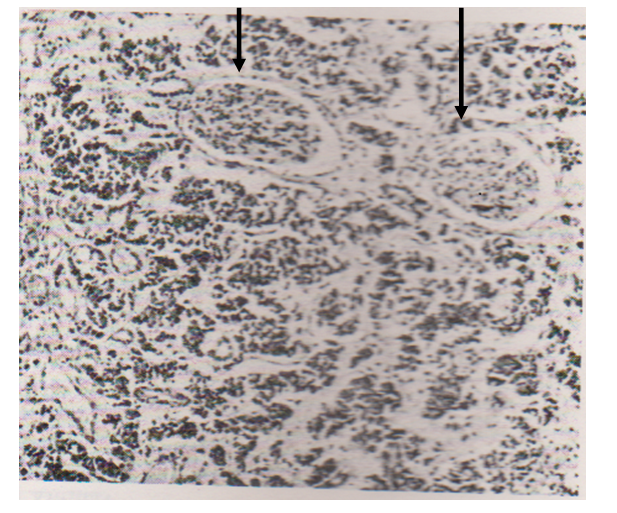

For instance, Willis11 was struck by the common feature of normal glomeruli standing out unscathed among parenchymatous metastases in the kidney? Figure 1 of my original paper. Let us go back to the 1842 original work of Bowman.12 He argued thus: “Hence must arise a greater retardation of the blood in the (glomerular) tuft, then occurs probably in any other part of the vascular system; a delay that must be increased by the tortuosity of the channels to be tranversed.” Note the words, “retardation” and “delay.” These phenomena must increase the commingling of cancer cells and red cells, i.e., the very essence of that Factor which I named as EANF.

Figure 1 Two arrowed unscathed glomeruli immersed in secondary growths.